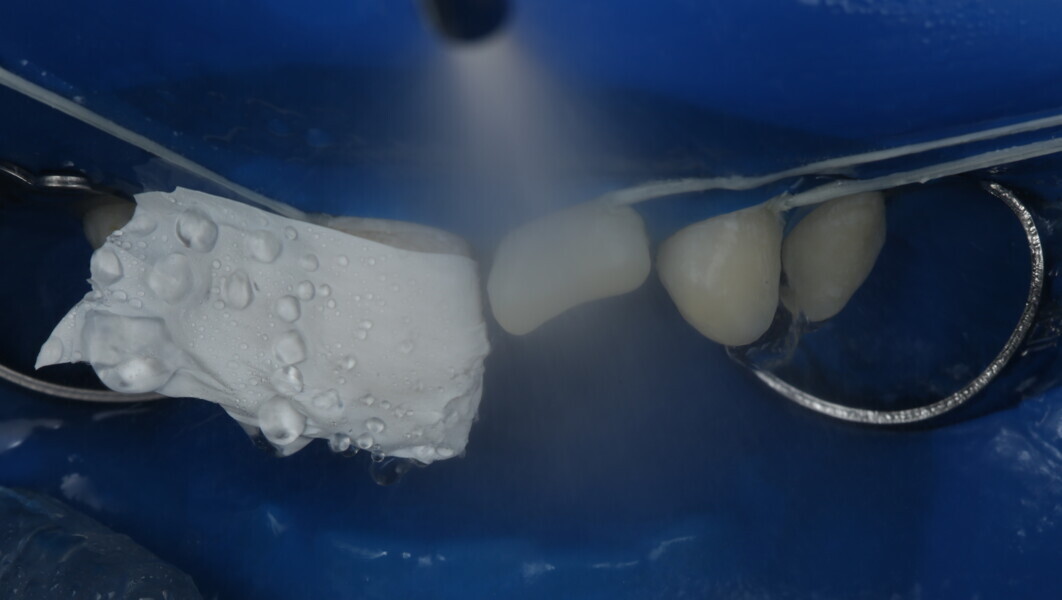

Fig 19-24: Contact build-up with band and wedge